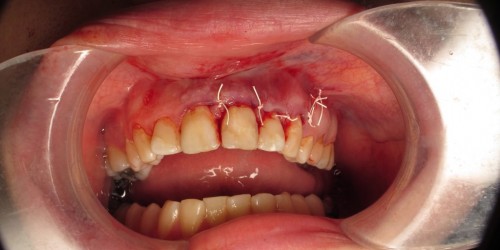

I had an apicoectomy ten weeks ago. Over all the procedure went well but I still have some strange sensation in the right side in my upper lip. The numbness is gone but there is a lot of taut Ness and at times a burning sensation in my lip.